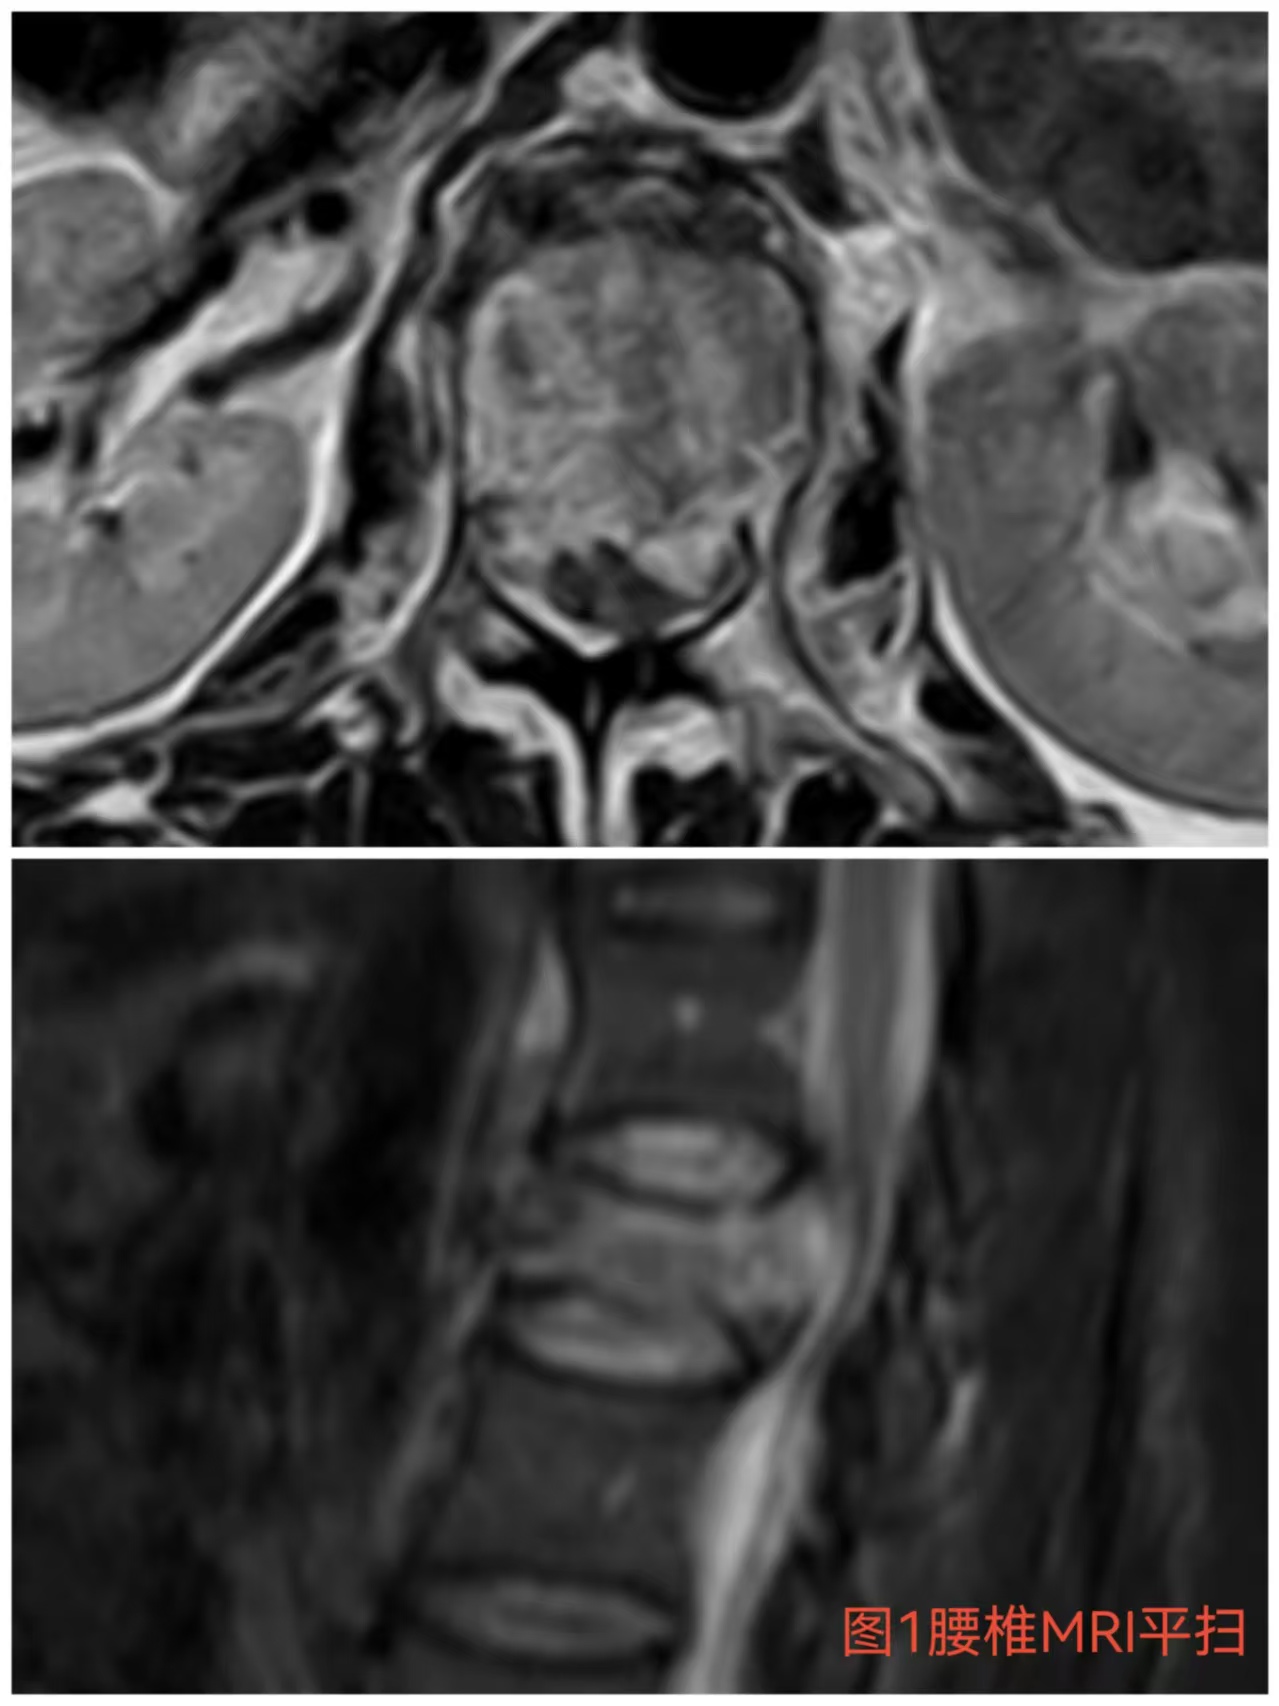

入院時(shí)患者躺在床上不能動(dòng)彈,眼神中透漏著深深的無助,對(duì)于她來說這種傷情無疑是沉重的,尤其是腹股溝以下感覺消失、雙下肢肌力0級(jí),這意味著其下肢無法活動(dòng)及站立,仿佛被命運(yùn)按下了暫停鍵;與病人及家屬充分溝通病情后,第一時(shí)間給予對(duì)癥治療,監(jiān)測(cè)患者生命體征,行腰椎核磁檢查(圖1)提示:腰1椎體爆裂性骨折,椎體后緣塌陷致骨性椎管狹窄,壓迫脊髓神經(jīng),結(jié)合患者病情及輔助檢查可診斷為:“L1椎體爆裂性骨折伴雙下肢截癱”。